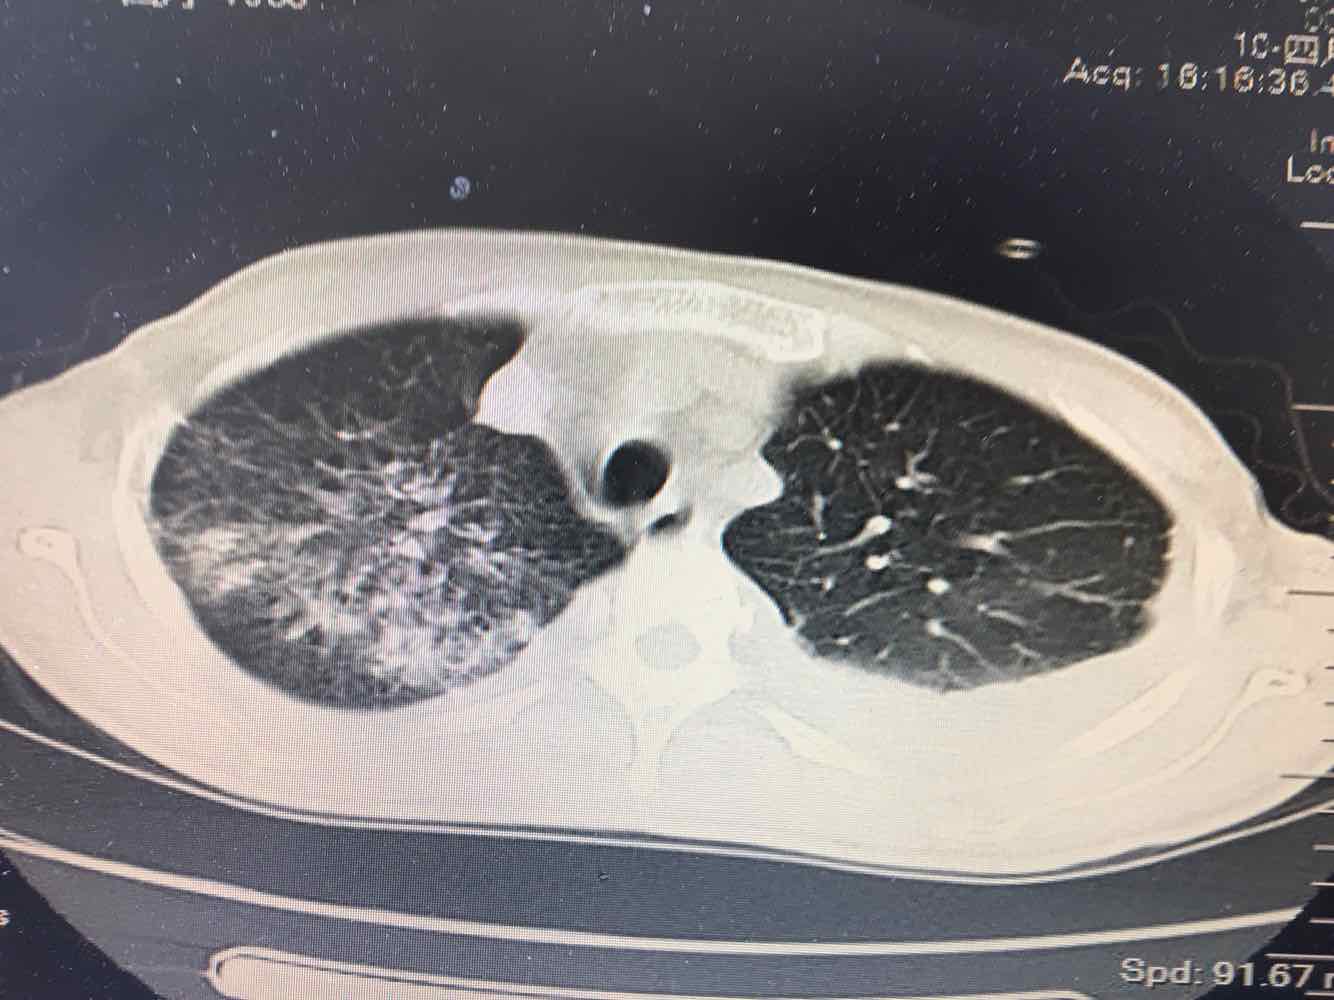

女,51岁,支气管扩张病史多年。慢性咳嗽咳痰喘息30年,加重1个月,无发热,气短为主,痰液不多,上腹不适,少尿。双肺干湿罗音。

图片

1/7

2/7

3/7

4/7

5/7

6/7

7/7